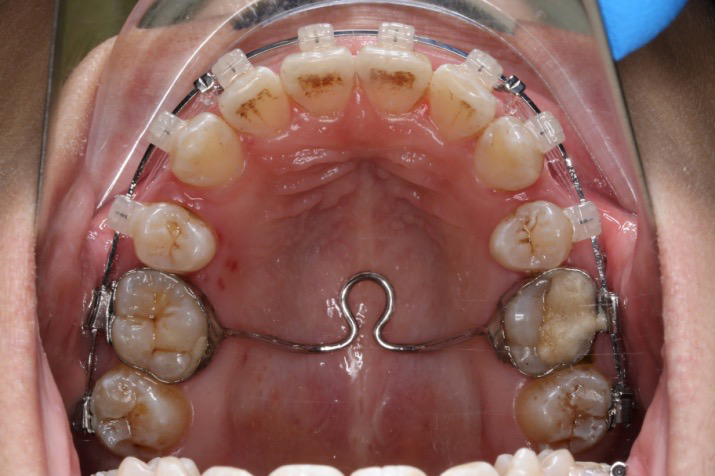

2017.10.07

2017.10.07  继续关间隙,下颌使用水平关间隙

下颌磨牙通过powerarm直立效果明显,下颌整平效果明显

2017.04.28

2017.05.26

2017.12.15

2017.12.15  继续关间隙